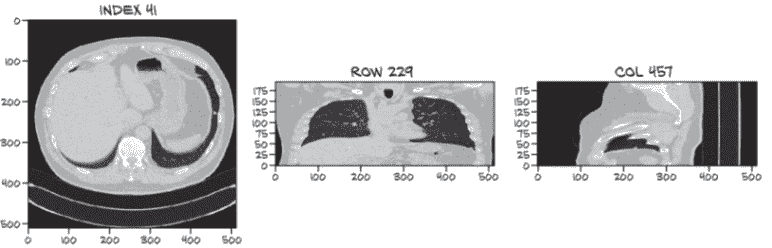

你能够在图 9.5 的三个视图中识别被标记为结节的白点吗?²

如果你需要提示,索引、行和列值可以帮助找到相关的密集组织块。你认为只有这些图像(这意味着只有图像–没有索引、行和列信息!)你能找出肿瘤的相关特性吗?如果你被给予整个 3D 扫描,而不仅仅是与扫描的有趣部分相交的三个切片呢?

注意 如果你找不到肿瘤,不要担心!我们试图说明这些数据有多微妙–难以在视觉上识别是这个例子的全部意义。

图 9.5 一张 CT 扫描,大约有 1,000 个对于未经训练的眼睛看起来像肿瘤的结构。当由人类专家审查时,只有一个被确定为结节。其余的是正常的解剖结构,如血管、病变和其他无问题的肿块。